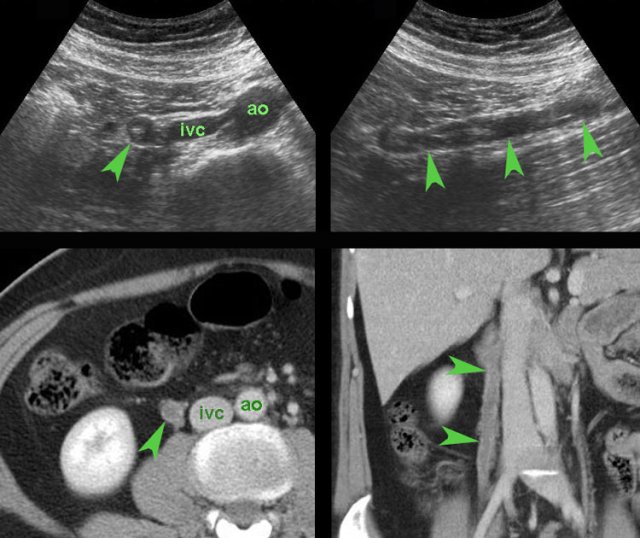

case 2

Here another case of an ischemic myoma.

The extrinsic location in this case suggests that this is a

pedunculated myoma (arrowheads).

This patient was successfully treated with analgesics and labor inhibitors.